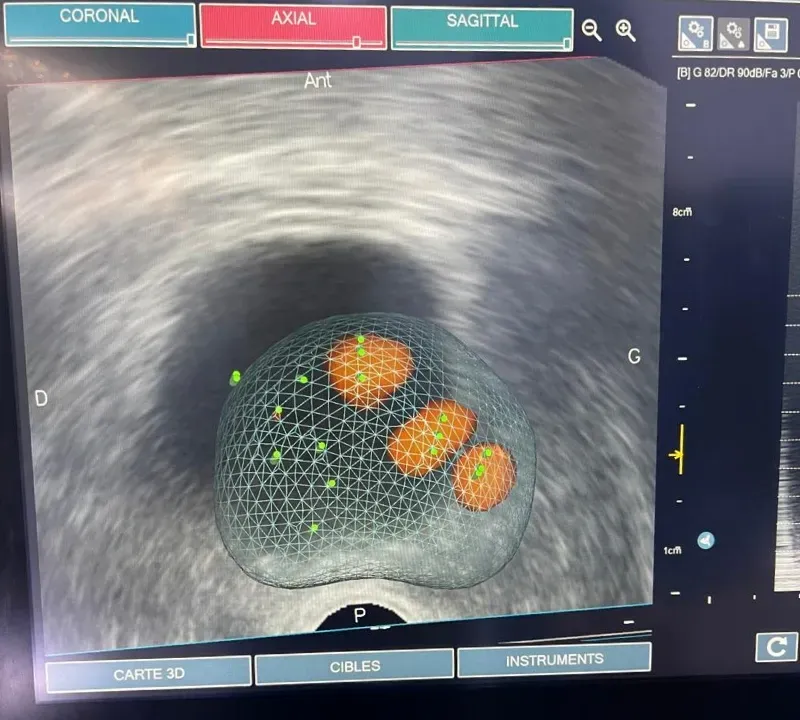

Biopsie prostatique ciblée

La biopsie prostatique ciblée repose sur la fusion d’images IRM et échographiques pour prélever des échantillons dans des zones suspectes de la prostate.Cette technique augmente considérablement la précision du diagnostic du cancer de la prostate.